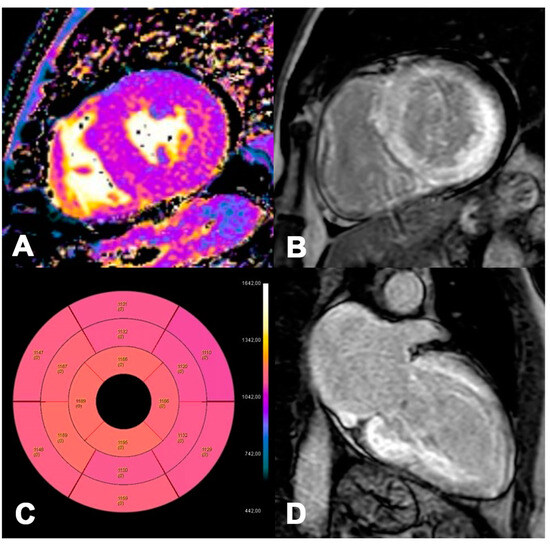

Figure 6.

AL 73-year-old patient diagnosed with endomyocardial biopsy. T1 Native Mapping (A) demonstrates a slight increase in value in all entire LV walls with subendocardial patterns. Circumferential subendocardial LGE of the anterior, antero-lateral, and infero-lateral LV wall in two-chamber short (B) and of the SIV to the apical segment in long axes (C). Bullseye map of T1 Native (D). LV, left ventricle; LGE, late gadolinium enhancement.

Figure 7.

ATTR 73-year-old patient diagnosed with endomyocardial biopsy. T1 Native Mapping (A) demonstrates abnormally high values in all entire LV walls in cardiac amyloidosis. Diffuse transmural LV and subendocardial RV LGE in two-chamber short (B) and long axes (C). Bullseye map of T1 Native (D).